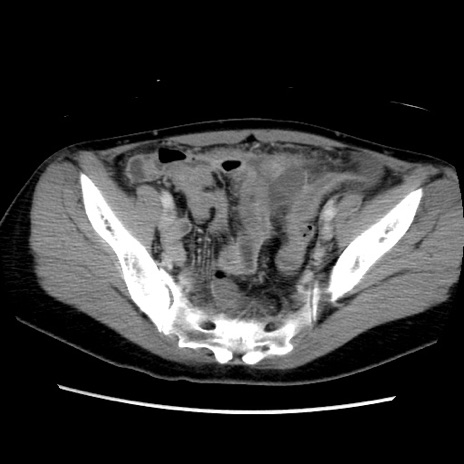

症例39(横断像)

【症例】40歳代女性

【主訴】上下腹部痛

【現病歴】2日目から下腹部痛あり。夜間は痛みで眠れなかった。昨日より上腹部痛と下痢が出現。臥位で痛みは軽快したため、休んでいた。本日になって臥位でも立位でも痛みが強くなってきたため救急要請。

【既往歴】子宮内膜症

【身体所見】部:平坦・軟、左上下腹部に圧痛あり、反跳痛あり。

【データ】WBC 21800、CRP 26.78